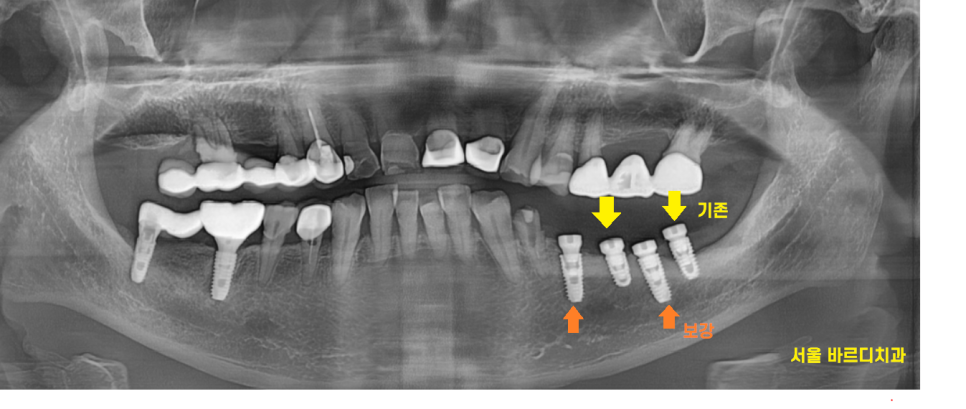

x-ray를 통해 확인해 보니

예전에 임플란트를 심었던 곳인데요.

특별한 점이 있다면 사랑니 부위에도

임플란트가 심어져있었습니다.

사랑니에 심어져있던 임플란트는

각도도 좋지 않고

뼈도 많이 녹아서 발치

앞쪽에 있는 임플란트는 뼈가

녹지 않아서 그대로 살려서 쓰기로 결정했습니다.

대신에 중간중간 새로운 임플란트를 심어

튼튼하게 보강은 필요했습니다.

23.08.23

이가 부서진 부위를 제거하고 나면

빈 공간이 생기는데

이 부분을 메꿀 필요가 있었기 때문입니다.

수술 직후 사진입니다.

기존 임플란트가 문제가 없다면

살려서 쓸 수 있답니다~!